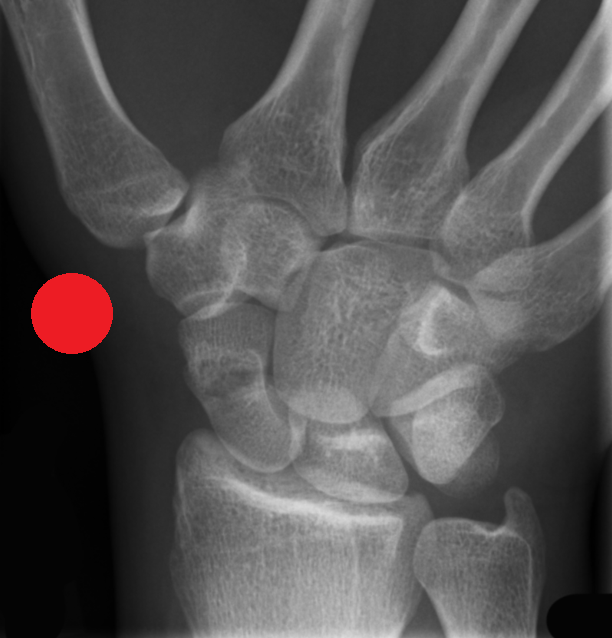

MSK CASES

www.mskradiology4u.co.uk

MSK Radiology Signs

http://www.gentili.net/signs